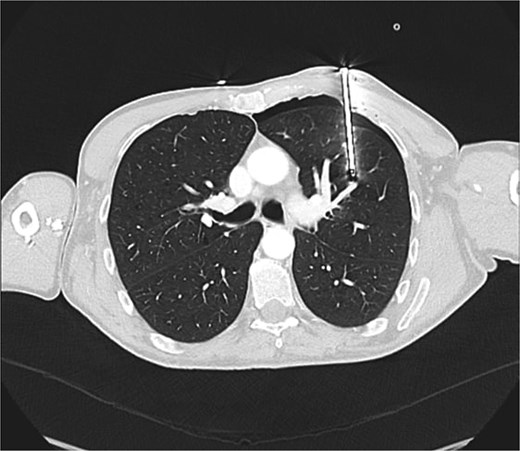

A 60-year-old male smoker presented following accidental discharge of a nail gun into his left chest. On arrival, he was asymptomatic with stable vital signs. Chest radiography showed a 10 cm nail within the left hemithorax and a small apical pneumothorax. Computed tomography (CT) imaging revealed the nail embedded in the upper lobe of the left lung, lying 3 mm from the anterior segmental branch of the pulmonary artery (Figs 1 and 2).

Axial CT chest demonstrating nail lodged in the left upper lobe, 3 mm from the anterior segmental branch of the pulmonary artery.